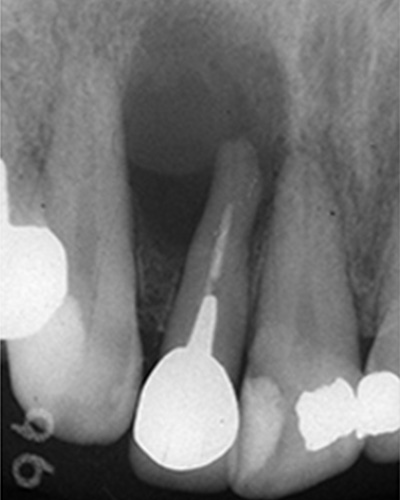

実際のケースを

こちらのレントゲン写真を見てください。どちらかの歯医者さんで神経を取っています。根管に入れる薬は白く映ります。赤矢印部分です。一番右側が模式図ですが、青い部分が薬、根っこの先の赤点が化膿している部分です。

薬がほとんど入っていないのがわかります。黄矢印部分です。青矢印まで薬が入らないといけないのですが、全く入っていません。その結果、根っこの先が黒くなっています。膿が貯まって化膿すると黒く写ってくるのです。

別な歯科医院で治してもらいました。薬が根の先まで入っているのがわかります(黄矢印)。 根尖の黒い影が消失しています(赤矢印)。骨が再生すると白く写るようになります。

①の写真はどちらかの歯医者さんで神経を取ってもらったレントゲン写真です。根っこの中に薬が全く入っていません。

②の模式図で青く描かれている部分が薬です。

根の先を見ると小豆ぐらいの大きさの黒い影が見えます。根の中でばい菌が繫殖し感染を起こすとこのような黒い影ができます。黒い影の部分は膿(ウミ)が貯まっています。こうなると腫れて痛みが出てくるのです。

③、④の写真はそれを治した後のレントゲン写真とその模式図です。白く映っている薬が根の先まできちんと入っているのが確認できます。そして根の先にあった黒い影が消えているのが分かります。根の先の炎症が治って、骨が再生すると白く映るのです。

実はこのケース、歯医者さんの神経を取る治療でこのような根っこの病気になってしまったのです。そこでこの患者さんは神経を取った歯医者さんではなく、別の歯医者さんに受診して、根っこの治療をして治したのです。